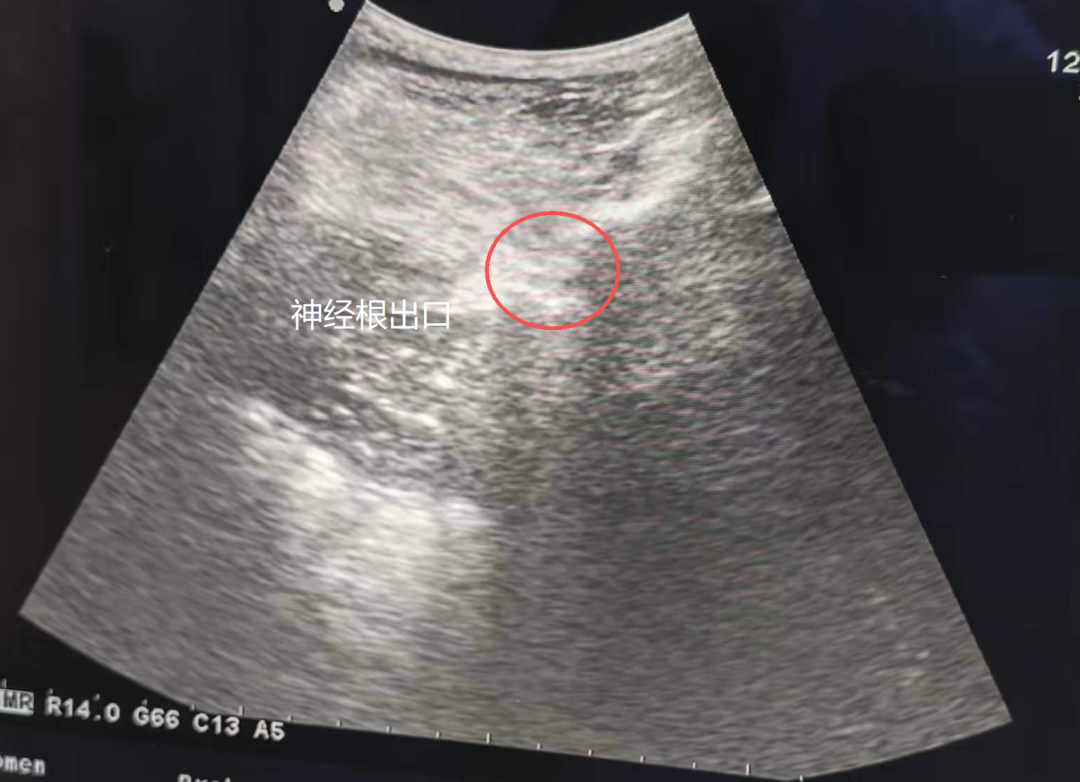

随后,吴树鑫医生为许先生制定了门诊彩超引导下的神经根阻滞治疗——简单说,就是在彩超的精准引导下,行相应神经根阻滞治疗后,许先生立马就感觉大腿不疼了,那种针扎、电击一样的刺痛感消失了。“太神奇了!折磨我十几天的疼,一下子就没了,终于能睡个安稳觉、吃顿踏实饭了!”许先生激动地说,困扰自己多日的难题解决了!